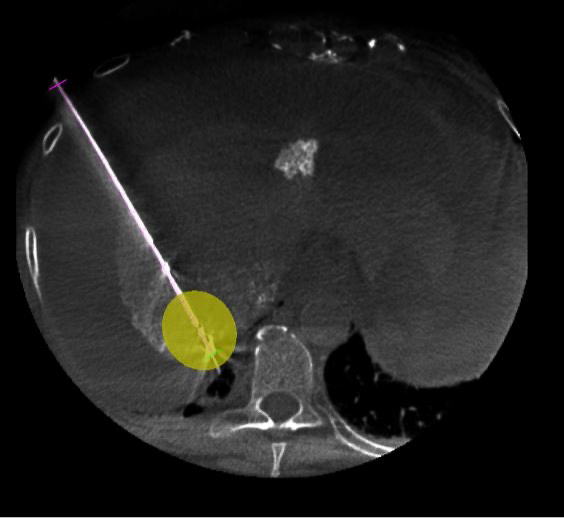

Equipped with sophisticated advanced image-guidance systems and multi-imaging modalities, our physicians may now better visualize and treat patients with complicated diseases. This system includes technology to make this easier in both 2D and 3D with dose reduction technology. It is equipped with integrated Intravascular Ultrasound. Vessel Navigation guidance, 2D Vessel Perfusion, 3D roadmap and Vessel quantitative measurements are offered as well. Vessel Navigator allows reuse of 3D vascular anatomical information from existing CTA and MRA datasets as a 3D roadmap overlay on live X-ray images. With its sophisticated visualization, it provides an intuitive and continuous 3D roadmap to guide you through vasculature during the entire procedure. The system is connected to our PACS system allowing us to visualize previous diagnostic images inside the room.

As the clinician moves the system, the image beam automatically maintains alignment with the patient, allowing more consistent visualization and enabling them to keep their focus on the treatment. In addition, the room has ability to perform cone-beam XperCT, which will allow us to move some interventional procedures from one of the CT scanners on the first floor of University, further freeing-up capacity for diagnostic CT.